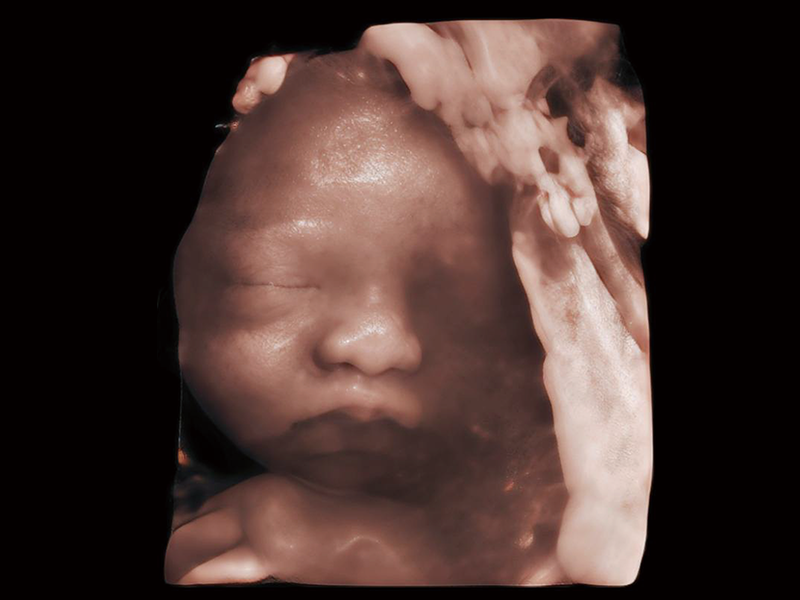

睿顏成像

多光源成像

S-Fetus? 鳳眼

臨床圖